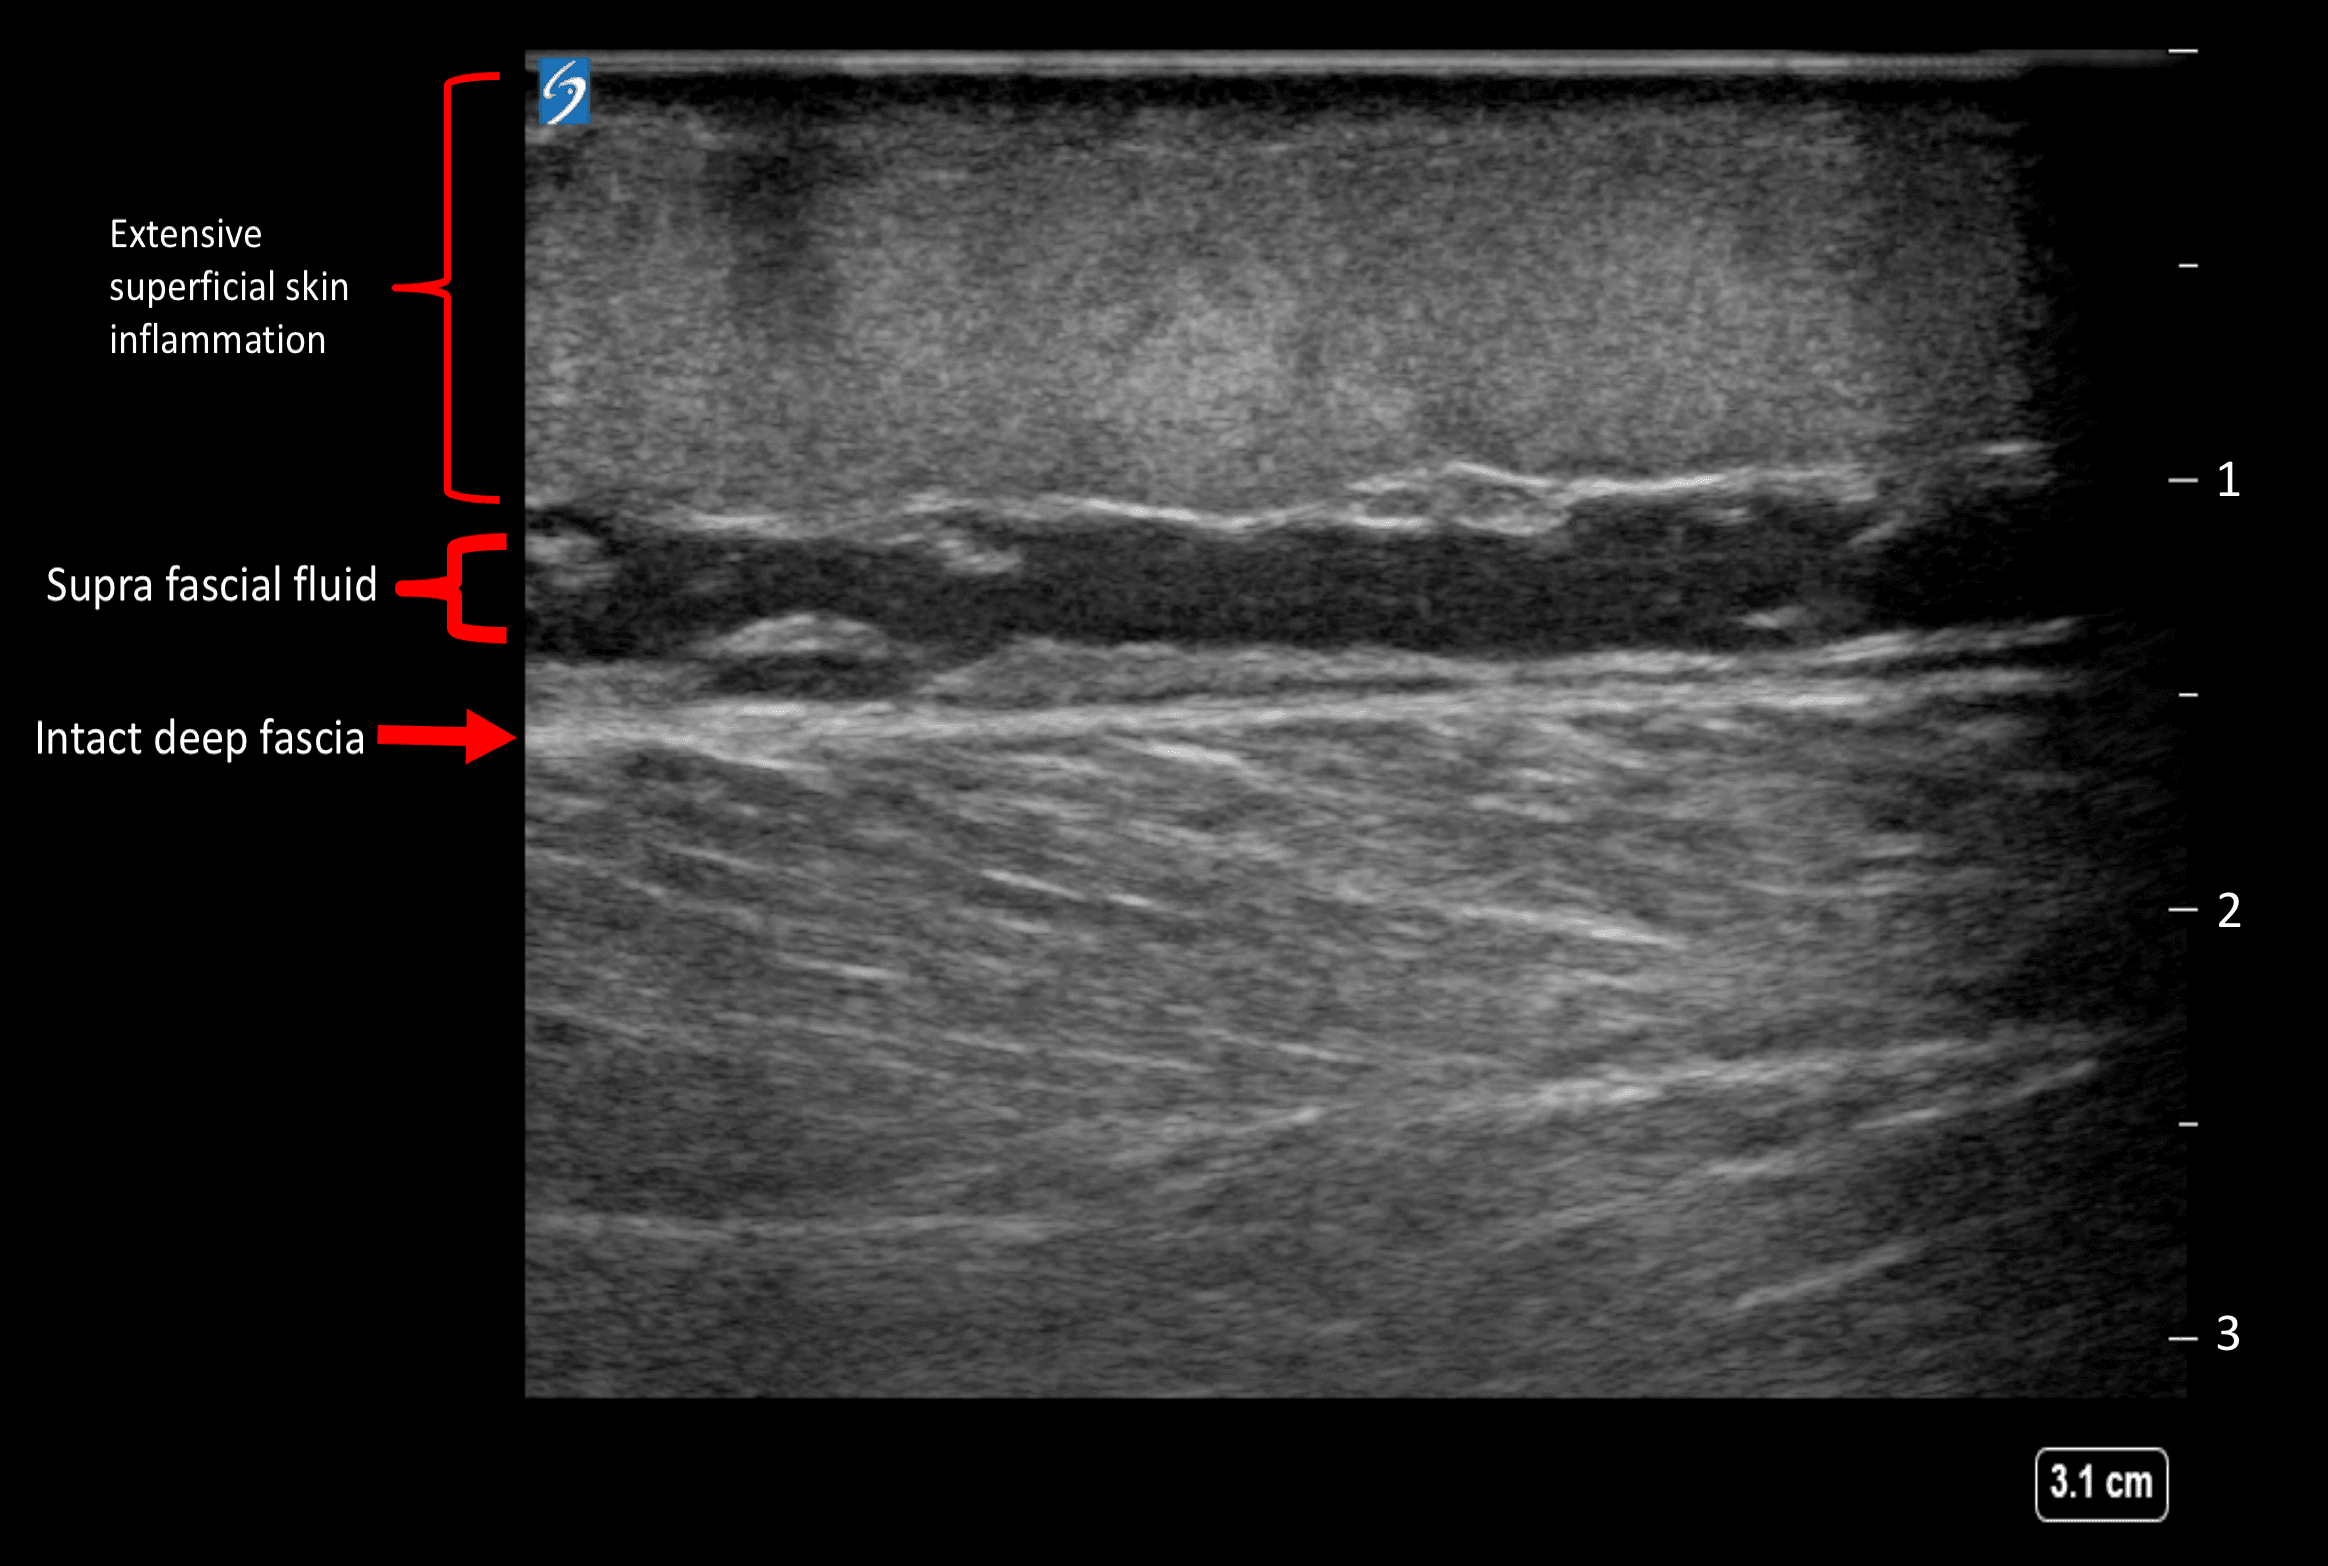

Urgent surgical consultation was obtained and broad-spectrum antibiotics were initiated. Soft tissue ultrasound was performed by linear probe and showed superficial cellulitis with no fascia thickening or sub-fascial fluids seen (clean fascia sign) as per Figure 2. Due to the high clinical suspicion, the patient was posted for urgent surgical debridement for possible necrotizing fasciitis. Intraoperative findings were only positive for superficial inflammatory process; the fascia was found healthy and intact. The patient was labelled as a case of complicated erysipelas and managed with daily dressing and antibiotics. The patient improved over a period of 2 weeks and was discharged home successfully.

Figure 2. soft tissue ultrasound showing superficial cellulitis with no fascia thickening or sub-fascial fluids seen (clean fascia sign).

In necrotizing fasciitis, there tends to be sonographic features such as thickened fascia, gas shadows, supra & sub-facial fluid collection (dirty fascia sign) [3]. This helps in guiding early diagnosis and recognition of such cases, hence prompt surgical intervention.